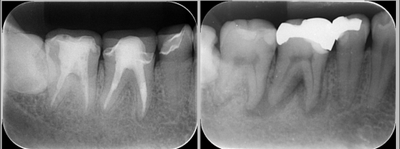

根管治療は“回数”より“設計”が重要

根管治療は、従来複数回の通院が必要とされることが多い。

しかし診断精度や設備、治療計画によっては、

症例に応じて比較的少ない通院回数で完結するケースもある。

重要なのは、

・感染状態の正確な評価

・マイクロスコープ下での精密処置

・治療後の被せ物までを含めた計画立案

である。

単に回数を減らすことではなく、

神経治療から補綴までを一連の流れとして設計することが、

渡航前治療では特に求められる。

さらに、根管治療が途中、もしくは治っていないで放置してしまった場合は、将来の抜歯のリスクが高くなってしまいますので注意が必要である。